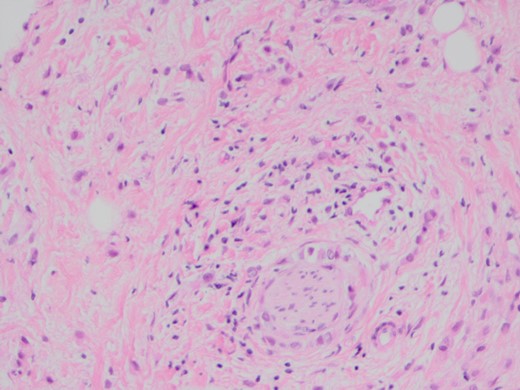

When she now presented with generalized abdominal pain, a CT scan of the abdomen was performed, revealing a lesion in the head of the pancreas measuring 7 × 4 cm2. This mass extended into the porta hepatis and towards the left lobe of the liver, opacification of the splenic vein and superior mesenteric veins was absent, and the confluence of the portal vein could also not be visualized (Fig. 1). Total bilirubin was 13 μmol/L (normal <20), raised ALT at 127 U/L (normal <34) and AST at 69 U/L (normal <31). ALP and GGT were also mildly raised at 135 U/L for ALP (normal 30–110) and 219 U/L for GGT (normal <38). Carcinoembryonic antigen and CA19.9, both markers of pancreatic cancer, were not raised. She was referred to a hepatobiliary surgeon for consideration of a pancreaticoduodenectomy, with the assumption of a primary pancreatic lesion. Due to suspected vascular involvement and potential peritoneal disease seen on the CT, she was regarded as an unsuitable candidate for a pancreaticoduodenectomy. To consider the use of palliative chemotherapy, a percutaneous biopsy for tissue diagnosis was performed. Histology demonstrated a poorly differentiated tumour, surrounded by benign pancreatic tissue with focal areas of perineural invasion by GATA3 positive epithelial cells. These cells also stained positive for ER, K19 and CEA, but negative for PR, B72.3, E-cadherin and HER2. The final diagnosis was poorly differentiated lobular breast carcinoma. Unfortunately, we were unable to compare the expression profiles between the pathology from the axillary dissection and the metastatic disease (Figs 2–4).

![The poorly differentiated carcinoma shows nuclear positivity for GATA3 (IPX). GATA3 is commonly mutated in breast carcinoma and has been reported as indicative of metastatic breast carcinoma [9, 10].](https://oupdevcdn.silverchair-staging.com/oup/backfile/Content_public/Journal/jscr/2018/5/10.1093_jscr_rjy111/1/m_rjy111f03.jpeg?Expires=1775737219&Signature=K-HdxtGF22L~AoSJEg4YzsCaGYtj9kEJT5inGpqLyjRHjbCDSpZHS1T-3CRoSphXuE6nLynlImss942o6mFqLodGzR4eL4zzXNRptkJ7qAWDJ1aw~UrVKdnCLvl2toWz3c7oa24UGmkJjpNbddyY--boKFBmWp4nG3E6hAnXTYP7tLMLcgmSM2c~lTGTiJ3aUX9ufTkwzxy2vmIPhEWvaKqsTytwCHTtFYCKiKPnR~DpwqfuTmZKztEGrwyxfFAhbHD8tAnJFWH67dDryDUYl7upf5OfIe33mfP~OwlZseZP4~glXAxrcvkujlYFHX5DplJJ8FUnxvLXO56ZGqWd2Q__&Key-Pair-Id=APKAIYYTVHKX7JZB5EAA)